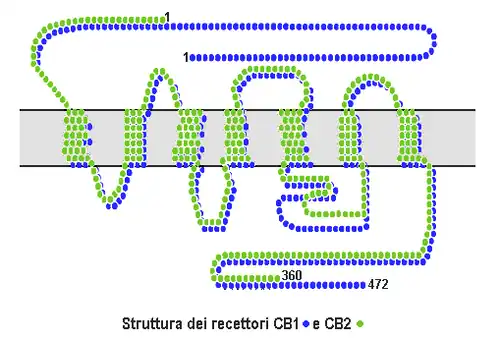

Claim: God gave us cannabinoid receptors so we could smoke pot all day.[77] "supertiger" argued, "That's right folks, our brains actually have receptors specifically active to THC. Did God create man with cannabinoid receptors to never use them?" and cited Ezekiel 34:29 and Isaiah 18:4-5.[77] This is basically an appeal to nature while asserting that Goddidit.

Reality: Cannibinoid receptors are activated by endocannabinoids,![]() i.e., cannibinoid chemicals that are naturally produced by the human body (e.g. arachidonoylethanolamine). Activation of cannibinoid receptors causes several physiological functions including gastrointestinal activity, cardiovascular activity and bone growth.[78][79]

i.e., cannibinoid chemicals that are naturally produced by the human body (e.g. arachidonoylethanolamine). Activation of cannibinoid receptors causes several physiological functions including gastrointestinal activity, cardiovascular activity and bone growth.[78][79]